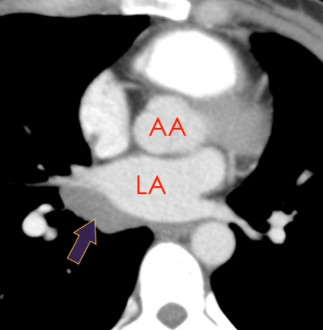

Récessus Aortique supérieur

Sinus Oblique

Sinus Veineux Pulmonaire